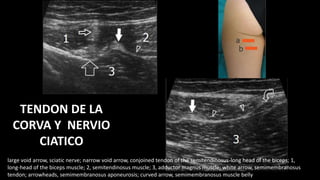

TENDON DE LA CORVA Y NERVIO CIATICO

asterisk, ischiatic tuberosity; arrows, common

tendon origin of the semitendinosuslong head of

biceps femoris

TENDON DE LA

CORVA Y NERVIO

CIATICO

large void arrow, sciatic nerve; narrow void arrow, conjoined tendon of the semitendinosus-long head of the biceps; 1,

long-head of the biceps muscle; 2, semitendinosus muscle; 3, adductor magnus muscle; white arrow, semimembranosus

tendon; arrowheads, semimembranosus aponeurosis; curved arrow, semimembranosus muscle belly